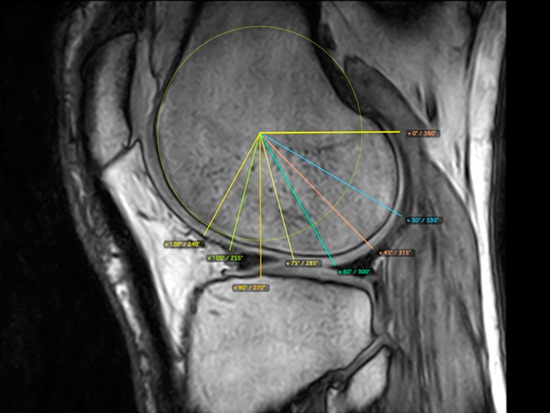

2.5. Evaluation of Knee Cartilage Thickness Using MRI

2.6. Medial and Lateral Femoral Condyle

2.7. Medial and Lateral Tibial Condyle